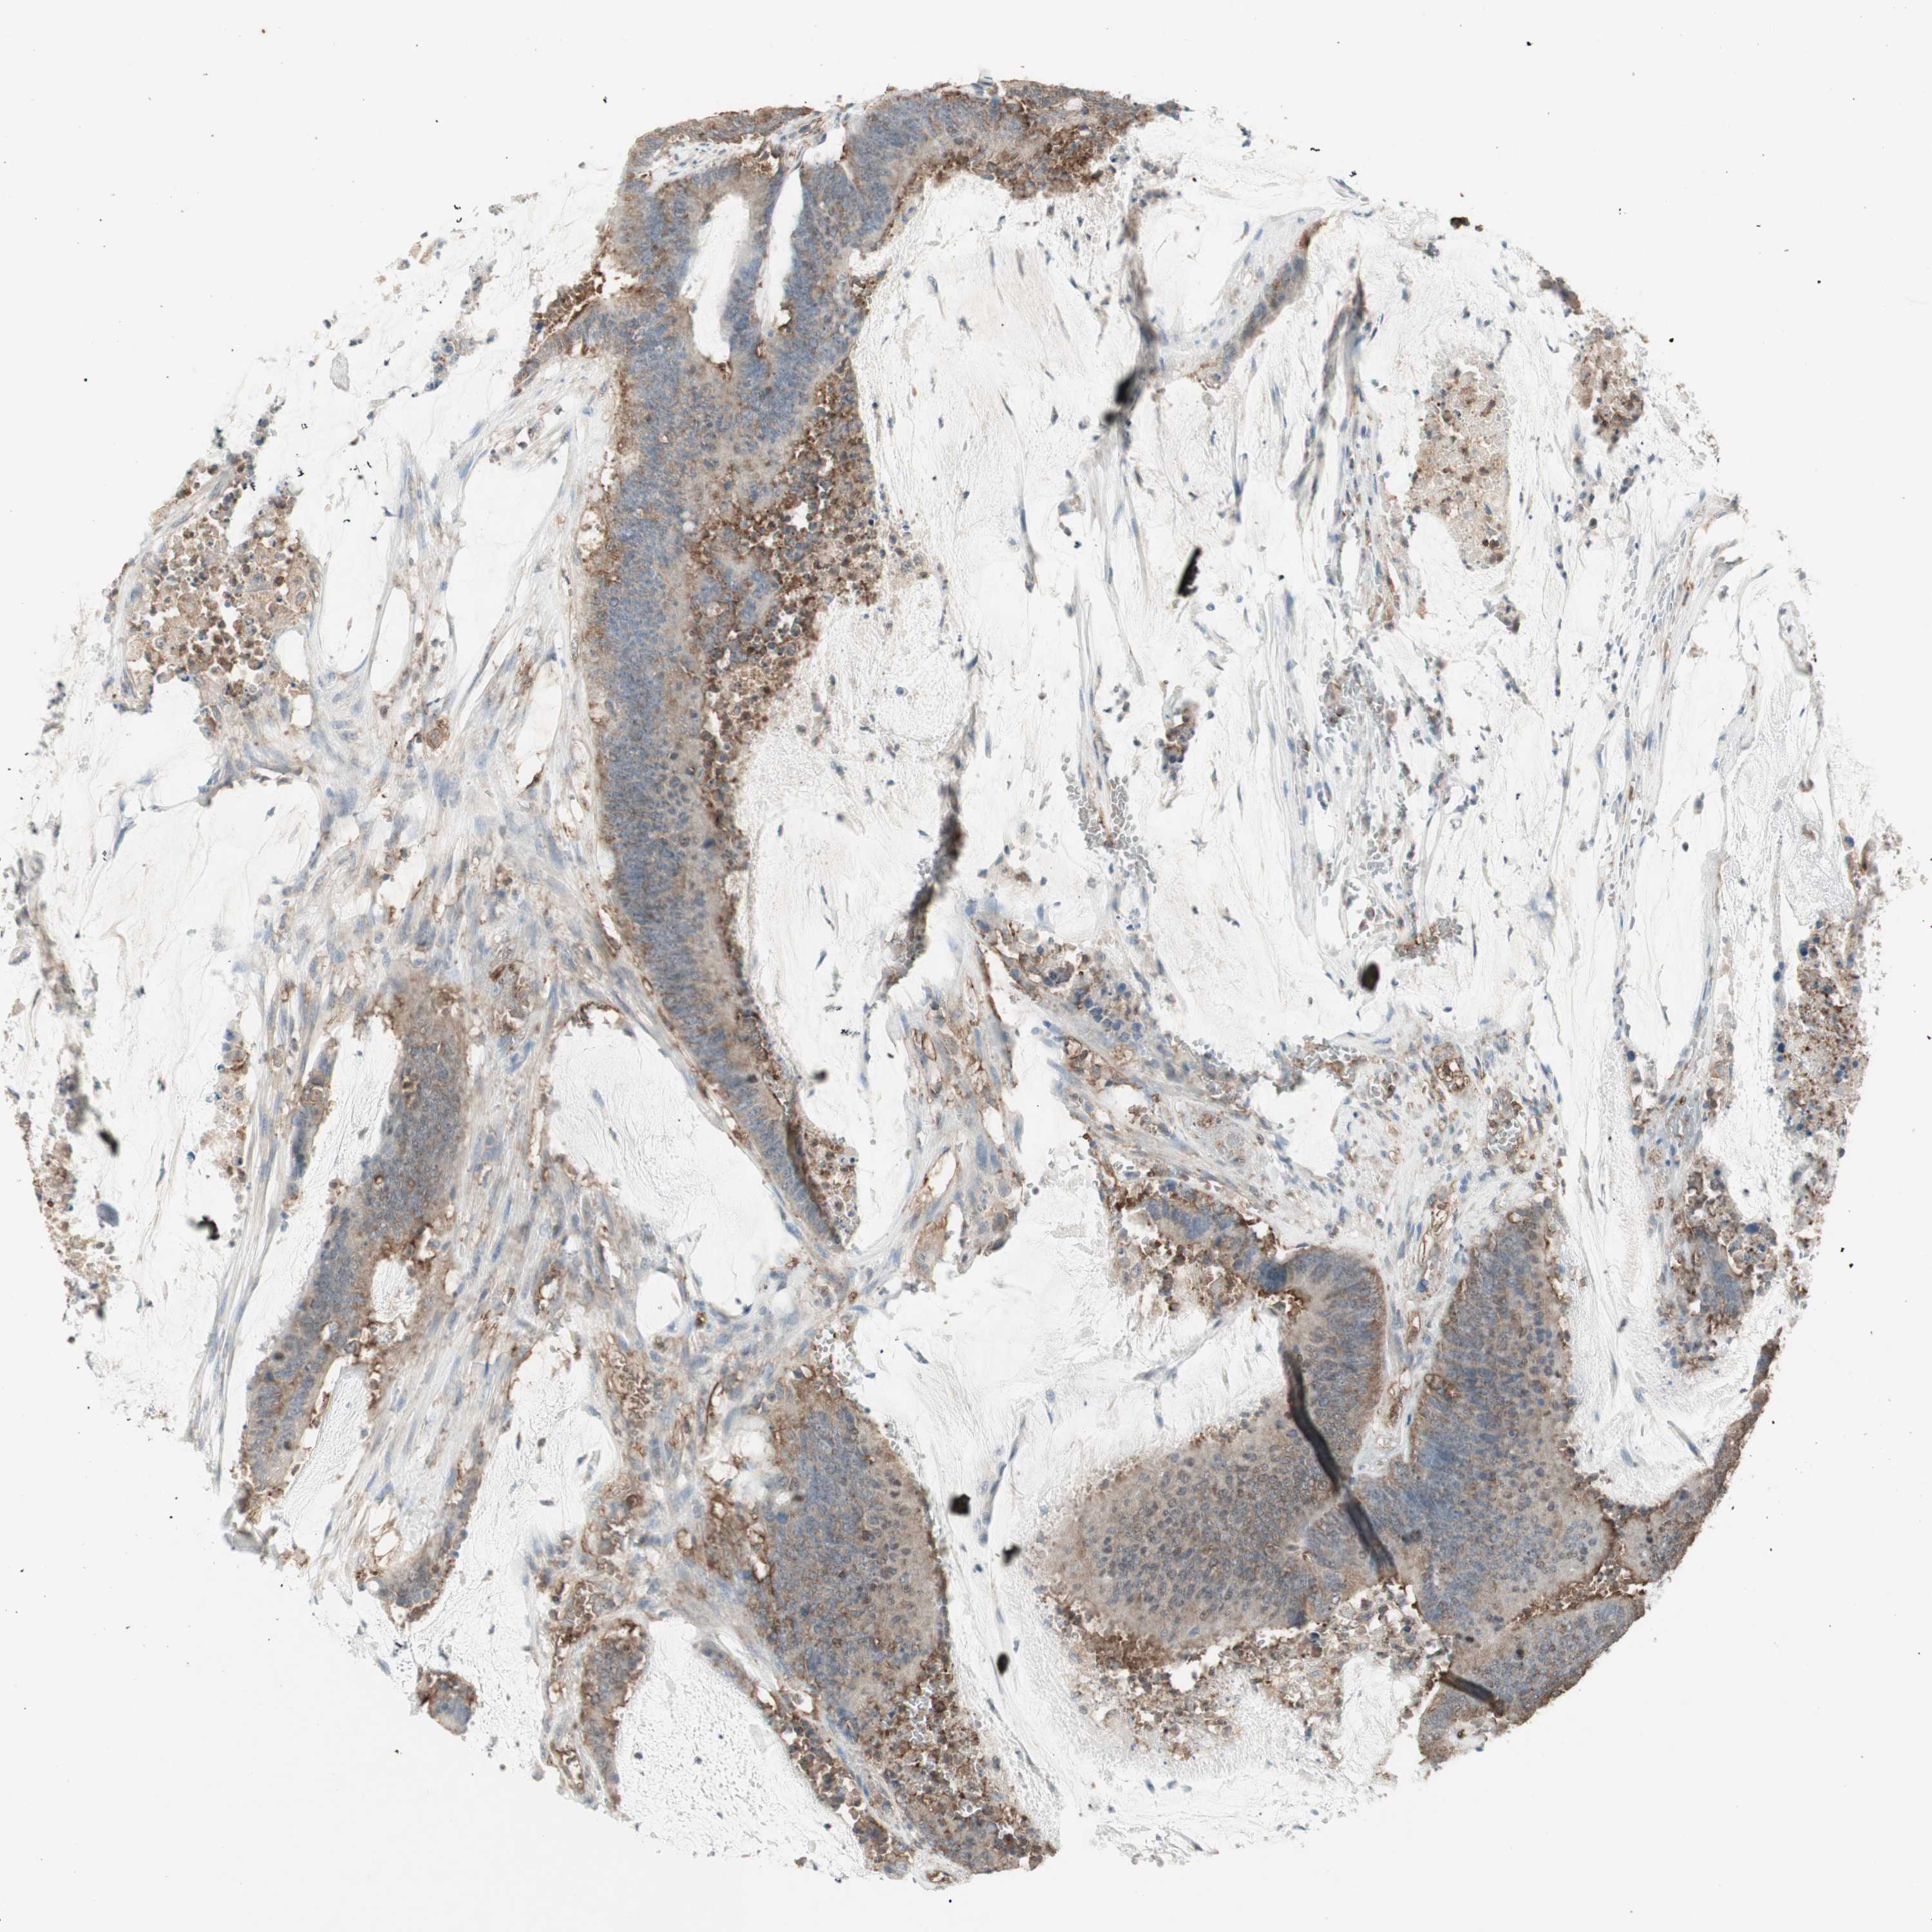

CANCER COLORECTAL CANCER Show tissue menu

Colorectal cancer

Human cancer

Colon adenocarcinoma